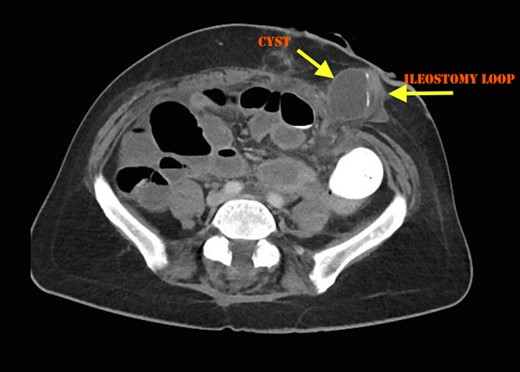

The patient recovered well with the stoma functioning well until Day 6, when she developed a small bowel obstruction. CT scan demonstrated cystic structure compressing the ileum loop within the anterior abdominal loop just before the stoma opening (Figs 1 and 2). Digital stomal examination and Foley’s catheter failed to pass through the stoma opening confirming the obstruction being at the abdominal wall. Failure of supportive measures, the patient was taken to theatre for revision of the stoma. Per stoma endoscopy was attempted with a gastroscope and which also failed to traverse the compression. At surgery, a semicircular skin incision was made adjacent to the stoma revealing what remained of the efferent ileal loop transformed into cystic mass abutting the stoma causing tight compression and was tightly adherent to the afferent ileal loop (Fig. 3). This was drained and partially excised with limited mobilization of the stoma. The remnant mucosa adherent to the afferent ileal loop was cauterized. Her recovery was unremarkable and was discharged Day 4 postsurgery. Histopathology of the partially excised cyst wall confirmed small bowel with viable mucosa showing mucosal flattening and complete loss of the villi.

Cross sectional CT Image showing compression of ileostomy opening.